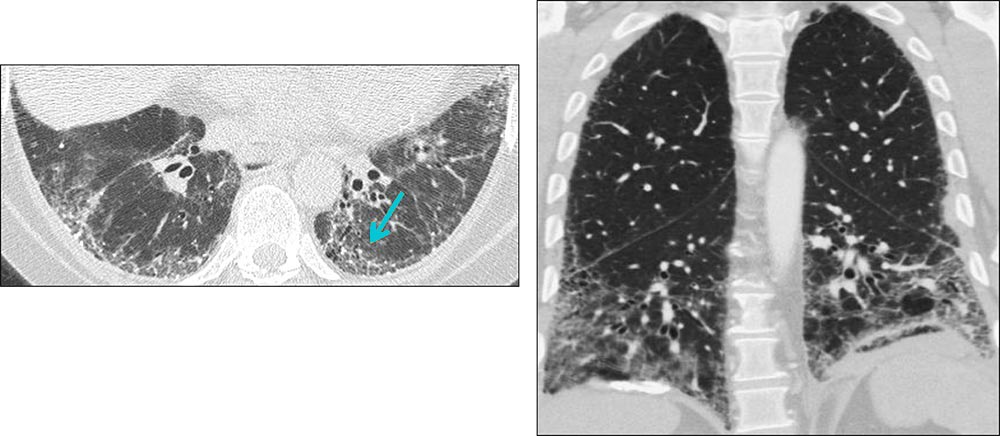

Axial and coronal HRCT images showing reticulation in two patients with IPF. Reticulation results from thickening of the interlobular or intralobular septa, and appears as several linear opacities that resemble a mesh or a net on HRCT scans. Usual interstitial pneumonia (UIP) is characterized by reticulation in the presence of traction bronchiectasis and often honeycombing.